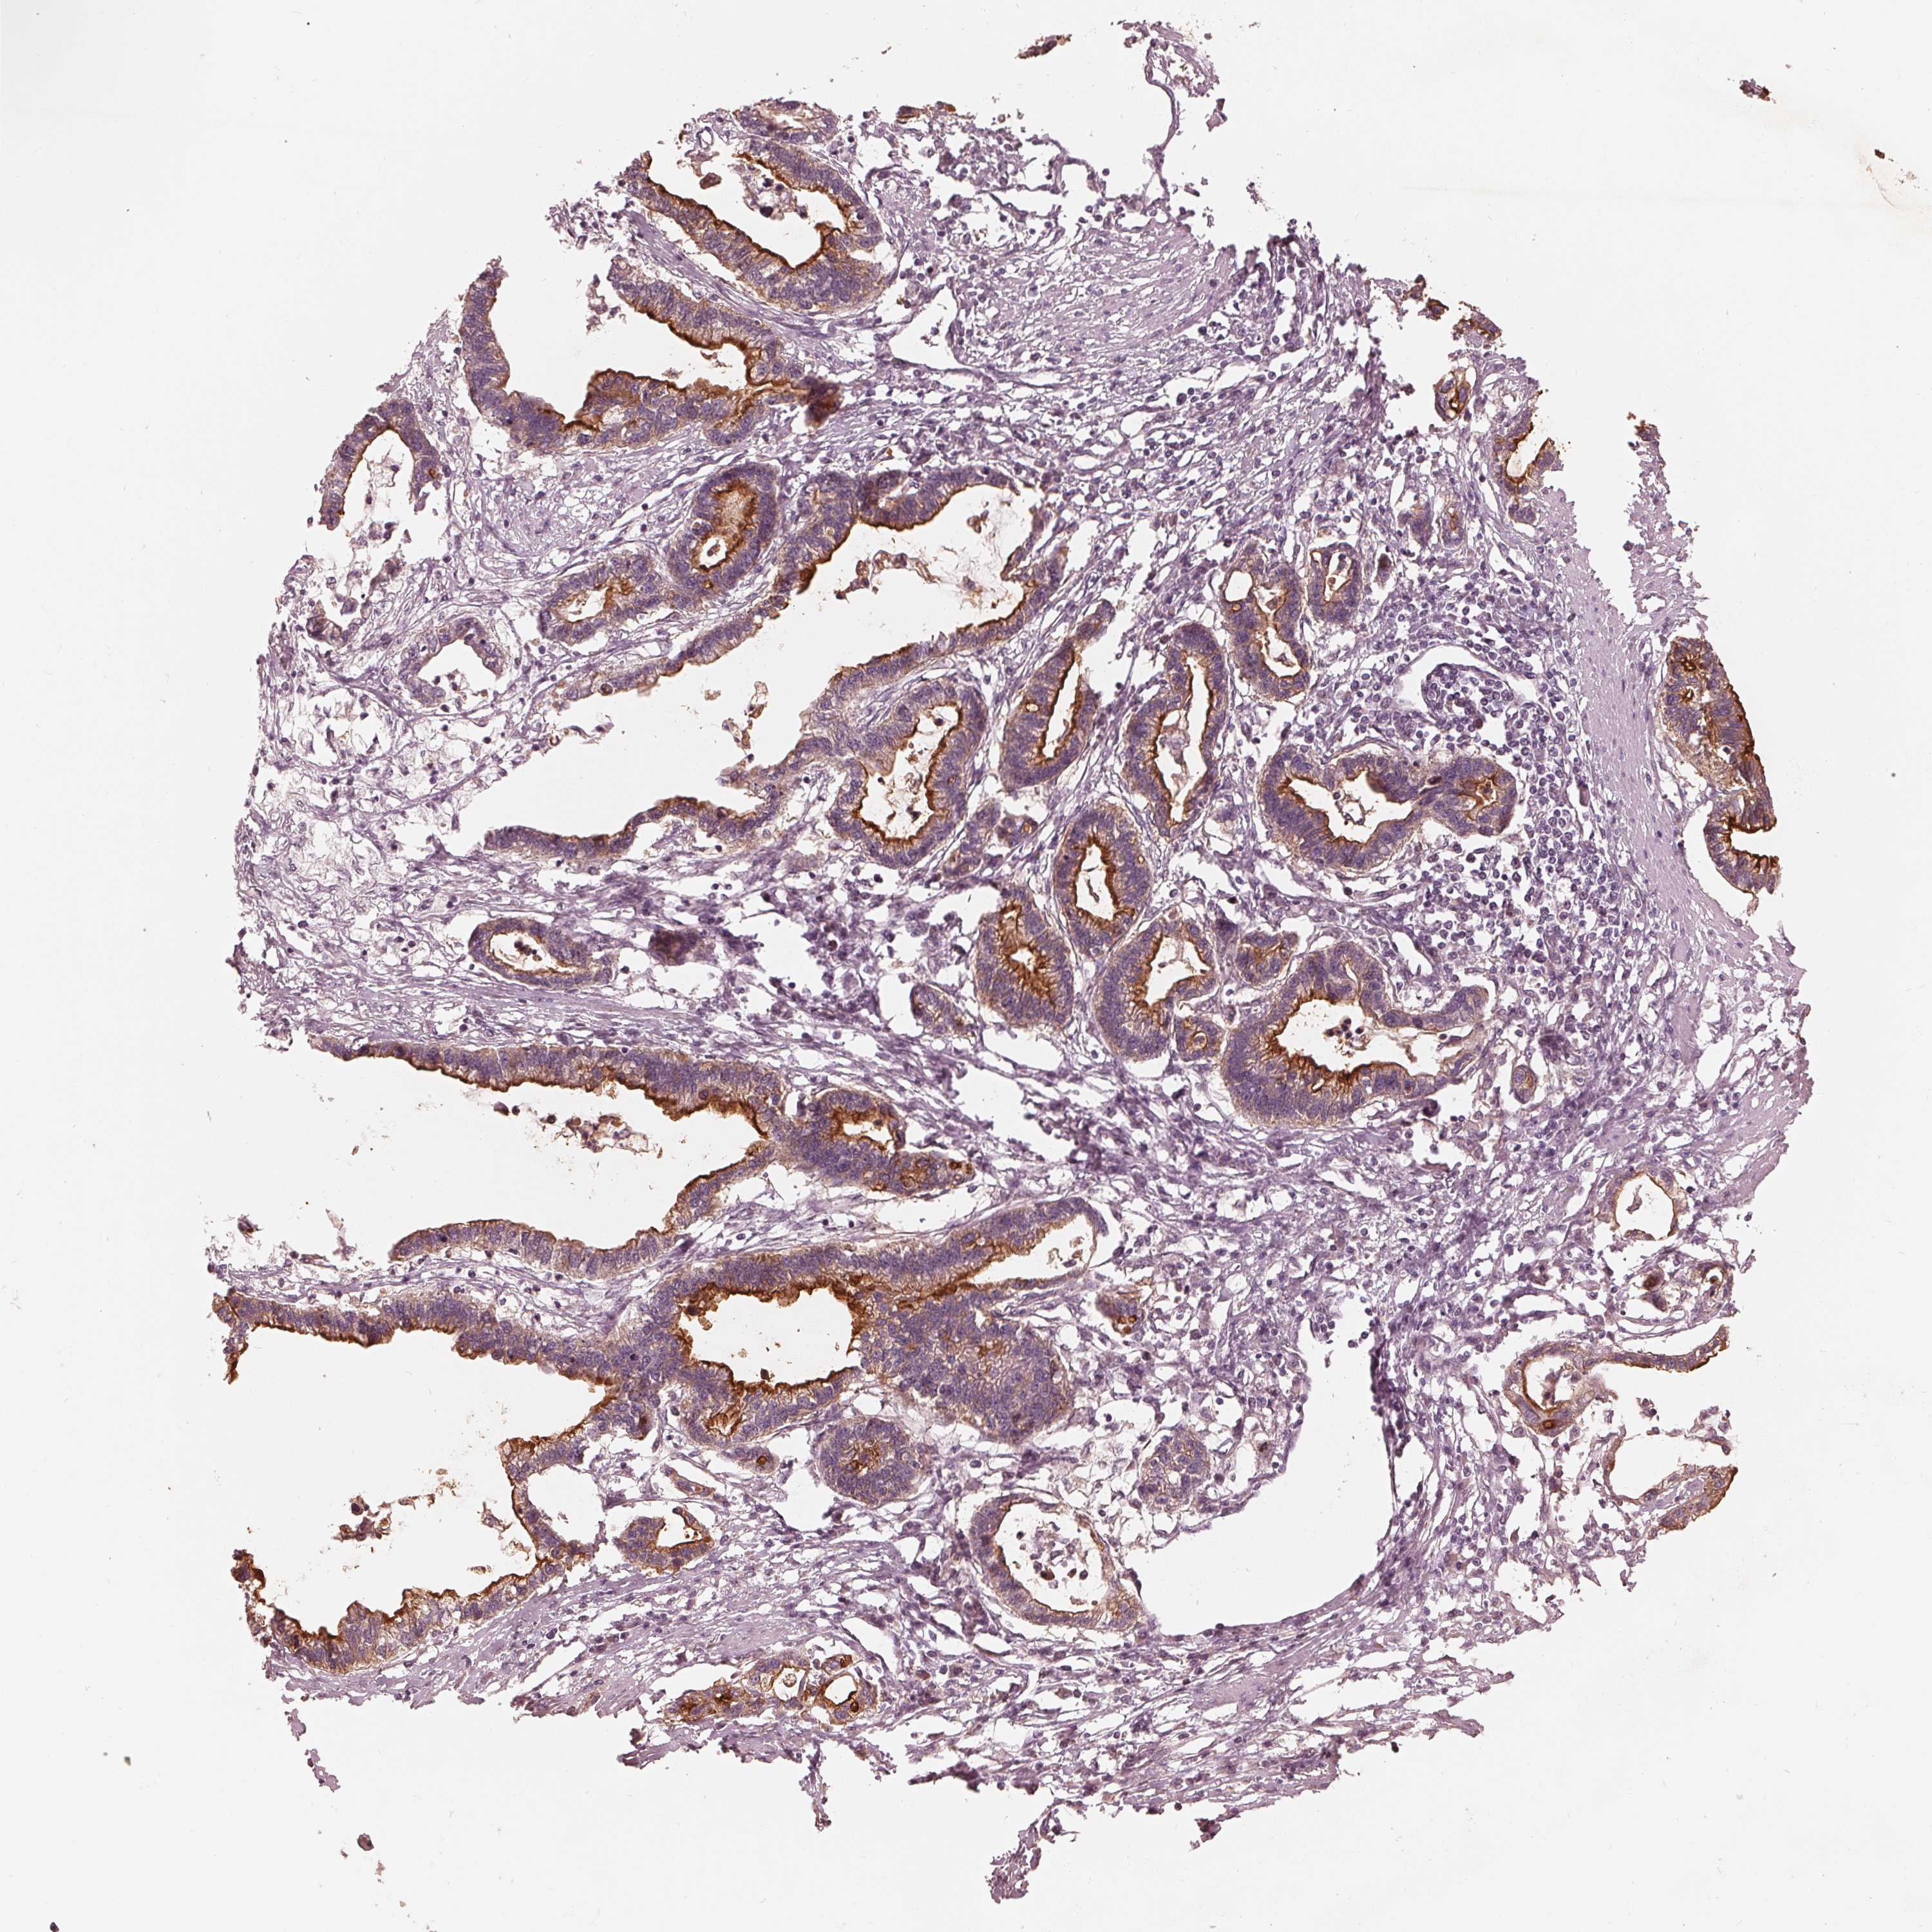

STOMACH CANCER - Protein expressioni

A mouse-over function shows sample information and annotation data. Click on an image to view it in a full screen mode. Samples can be filtered based on level of antibody staining by selecting one or several of the following categories: high, medium, low and not detected. The assay and annotation is described here.

Note that samples used for immunohistochemistry by the Human Protein Atlas do not correspond to samples in the TCGA dataset.

Antibody stainingi

Antibody staining in the annotated cell types in the current human tissue is reported as not detected, low, medium, or high, based on conventional immunohistochemistry profiling in selected tissues. This score is based on the combination of the staining intensity and fraction of stained cells.

Each image is clickable and will lead to virtual microscopy that enables deeper exploration of all samples and also displays staining intensity scores, fraction scores and subcellular localization as well as patient and tissue information for each sample.

Antibody HPA066695

Staining

High

Medium

Low

Not detected

Intensity

Strong

Moderate

Weak

Negative

Quantity

>75%

75%-25%

<25%

None

Location

Nuclear

Cytoplasmic/membranous

Cytoplasmic/membranous,nuclear

Adenocarcinoma, NOS